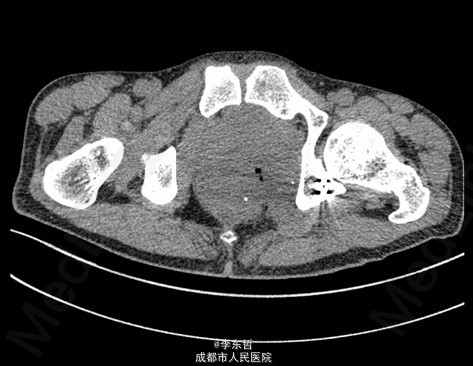

查体:臀部、会阴部、下腹部未触及包块,左下肢前内侧皮肤感觉较对侧减弱,双侧膝反射、跟腱反射正常引出,肛周皮肤感觉减退,直肠指检可触及质韧包块,活动度较差。双下肢肌力5级,双下肢各关节活动度可。 辅查:外院增强CT示:盆腔左侧壁见团块状软组织密度影,密度不均,其内见多发斑块高密度影,病灶大小约9.4*7.6cm,增强后强化不明确。我院X片示:左侧闭孔及耻骨区见不均匀高密度影,大小约6.2*6.7cm。我院MRI示:盆腔左份见长T1长T2肿块影,大小约10.3*7.7*10.5cm,向前推挤膀胱,向右推挤前列腺。我院骨扫描显示:耻骨联合及左侧耻骨支核素浓集。